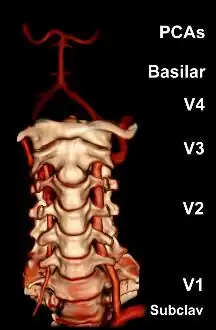

The vertebral arteries arise from the subclavian artery, and run through the transverse foramen of the upper six vertebrae of the neck. After exiting at the level of the first cervical vertebra, its course changes from vertical to horizontal, and then enters the skull through the foramen magnum. Inside the skull, the arteries merge to form the basilar artery, which joins the circle of Willis. In total, three quarters of the artery are outside the skull; it has a high mobility in this area due to rotational movement in the neck and is therefore vulnerable to trauma. Most dissections happen at the level of the first and second vertebrae. The vertebral artery supplies a number of vital structures in the posterior cranial fossa, such as the brainstem, the cerebellum and the occipital lobes. The brainstem harbors a number of vital functions (such as respiration) and controls the nerves of the face and neck. The cerebellum is part of the diffuse system that coordinates movement. Finally, the occipital lobes participate in the sense of vision.[1]

Subarachnoid hemorrhage due to arterial rupture typically occurs if the dissection extends into the V4 section of the artery. This may be explained by the fact that the arterial wall is thinner and lacks a number of structural supports in this section.[1][3][17]